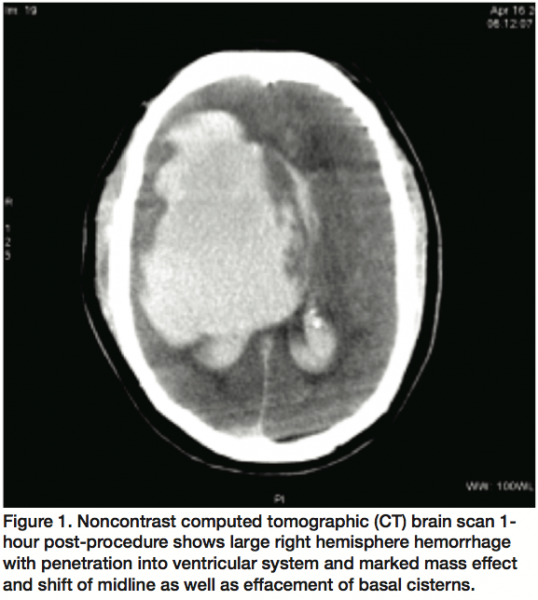

There was one incidence of intracerebral hemorrhage in the cohort (0.2%). This patient was a 70-year-old Caucasian male who was symptomatic from multiple recurrent TIAs with extensive morbidities including: diabetes mellitus, hypertension, chronic obstructive pulmonary disease (COPD), hyperlipidemia, and coronary artery disease (CAD). Notably, he experienced multiple ischemic events in the 5 years prior to the procedure, including a lacunar infarct in 2002, a left occipital stroke in 2004, and multiple incidences of left leg weakness thought to be attributed to TIAs in the days to weeks prior to the procedure. A 4-vessel angiogram identified 99.9% stenosis of the right internal carotid artery, 25%-50% stenosis of the contralateral internal carotid artery, and 50%-75% stenosis of the distal vertebral artery. Bivalirudin was administered in a single bolus (0.75 mg/kg) and infusion (1.75 mg/kg/hr). Antithrombotic therapy consisted of 325 mg aspirin, 600 mg clopidogrel, and adjunctive use of a single bolus (180 mcg/kg) of eptifibatide. A right carotid artery stent was successfully deployed and the final result showed minor irregularity. The patient exhibited signs of altered consciousness approximately 30 minutes post-procedure and a CT showed a massive ipsilateral intracranial hemorrhage (Figure 1).